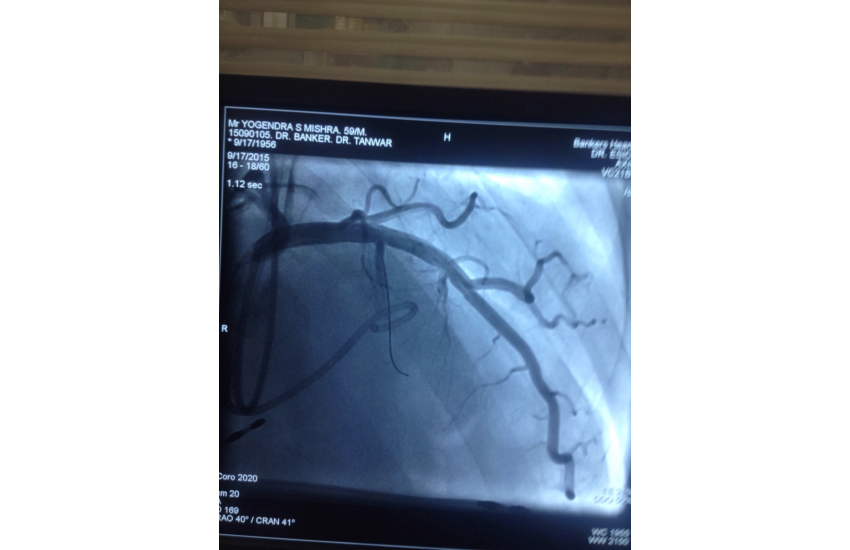

CAG revealed normal coronaries,holter shows sinus bradycardia,RBBB with LAHB,intermittent AF, TMT shows blunted chronotropic response and hypotensive response so he has been planned for PPI with back up of pacemaker patient treated with beta blockers and corderone,after 7 days of PPI,he has undergone alcohol septal ablation successfully,prior his dynaemic gradient was 50 mmhg in rest n 80 mmhg with exercise which reduced to 20mmhg after procedure. Now patient is under close follow up so will continue updating.